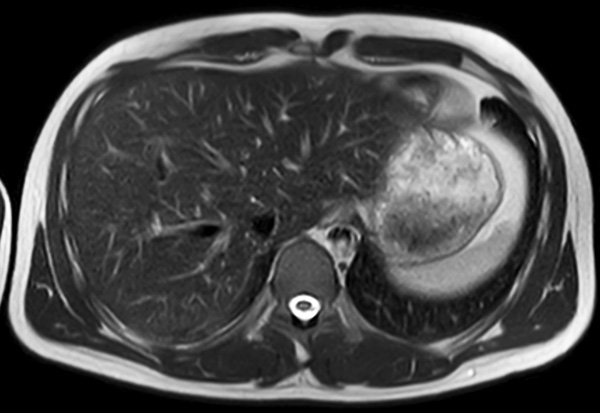

Axial T2w MultiVane XD (high res)

Axial T2w MultiVane XD SPIR (fast)